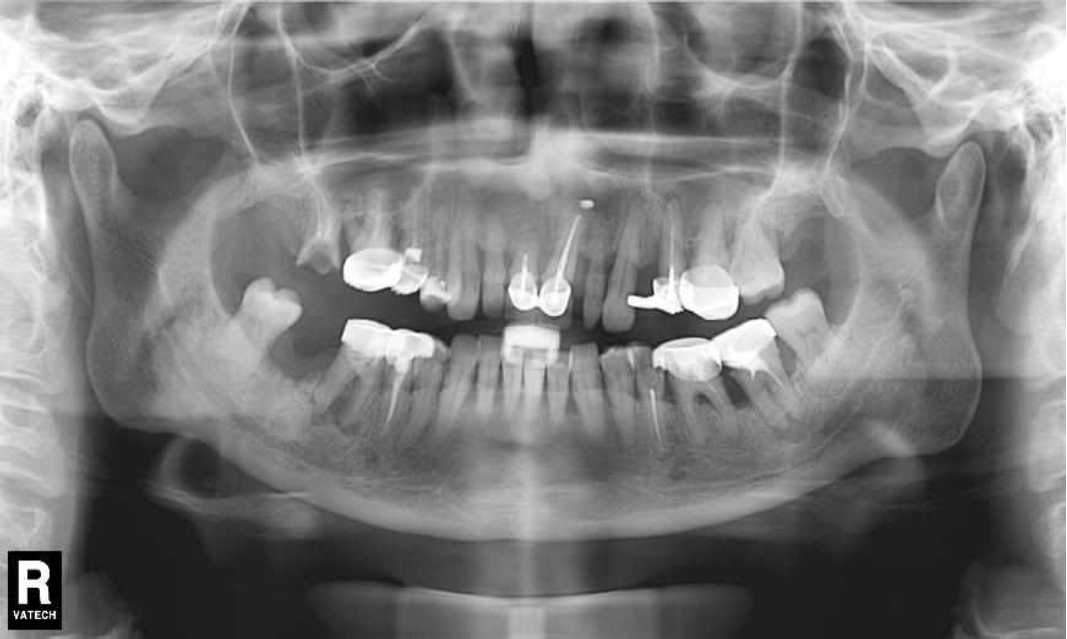

Ранее у пародонтолога не наблюдалась. При осмотре выявлены: неудовлетворительная индивидуальная гигиена полости рта, пародонтальные карманы до 7 мм, обильная кровоточивость и гноетечение из пародонтальных карманов, подвижность зубов 4.2, 4.1, 3.1, 3.2 II степени, обильные над- и поддесневые зубные отложения (рис. 1). На ортопантомограме отмечается резорбция костной ткани до ½ длины корня, очаги остеопороза (рис. 2). Пациенту был поставлен диагноз хронический генерализованный пародонтит тяжелой степени тяжести. При осмотре была составлена пародонтограмма с использованием компьютерного зондирования (рис. 3).

Рис. 1. Внешний вид

Через 6 месяцев при осмотре выявлен удовлетворительный уровень индивидуальной гигиены, отсутствие участков кровоточивости и гноетечения (рис. 4), пародонтальные карманы уменьшились в размерах (рис. 5). Пациент отмечает значительные улучшения. После стабилизации пародонтологического статуса пациент направлен для дальнейшего ортопедического лечения.

Рис. 4. Динамика результата через 6 месяцев

Рис. 5. Пародонтограмма с использованием компьютерного зондирования через 6 месяцев